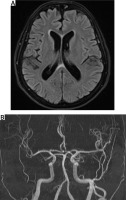

Head magnetic resonance angiography (MRA) and venography with contrast were within normal limits (Fig. 2). Erythrocyte sedimentation rate and CRP levels were normal. The halo sign on both temporal and axillary artery ultrasound was absent. The Southend Giant Cell Arteritis Probability Score (GCAPS) score was 15 [1].